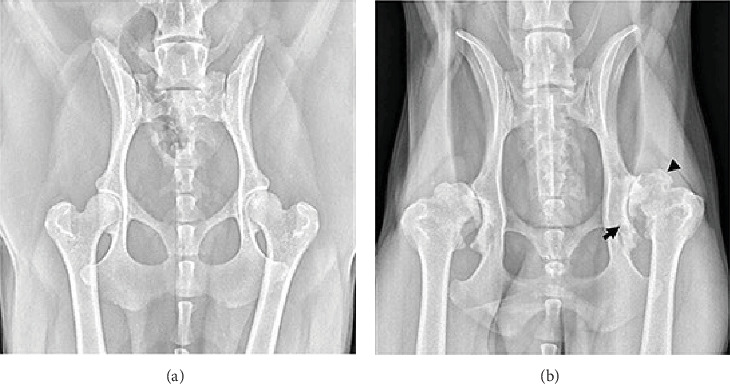

Abstract Image